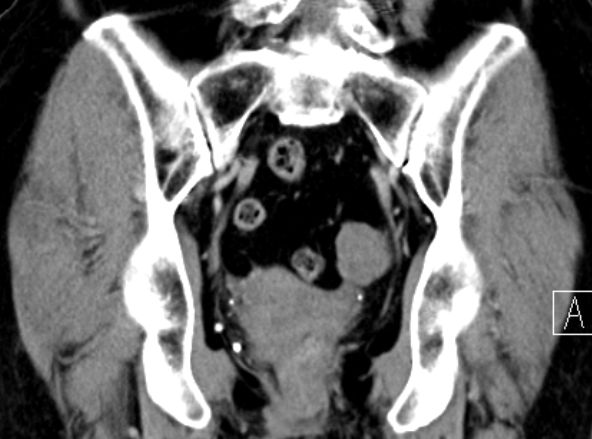

| Diagnostik | 70-jährige Frau mit einer RF des linken Adnex. Histologisch adulter Granulosazelltumor FIGO Ia.![]() |

| Morphologie | meistens unilaterale, solide (auch multizystisch) mit grauweißer oder gelblicher Schnittfläche. | |||